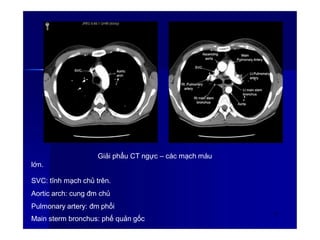

Giải phẩu CT ngực – các mạch máu

lớn.

SVC: tĩnh mạch chủ trên.

Aortic arch: cung đm chủ

Pulmonary artery: đm phổi

Main sterm bronchus: phế quản gốc

63